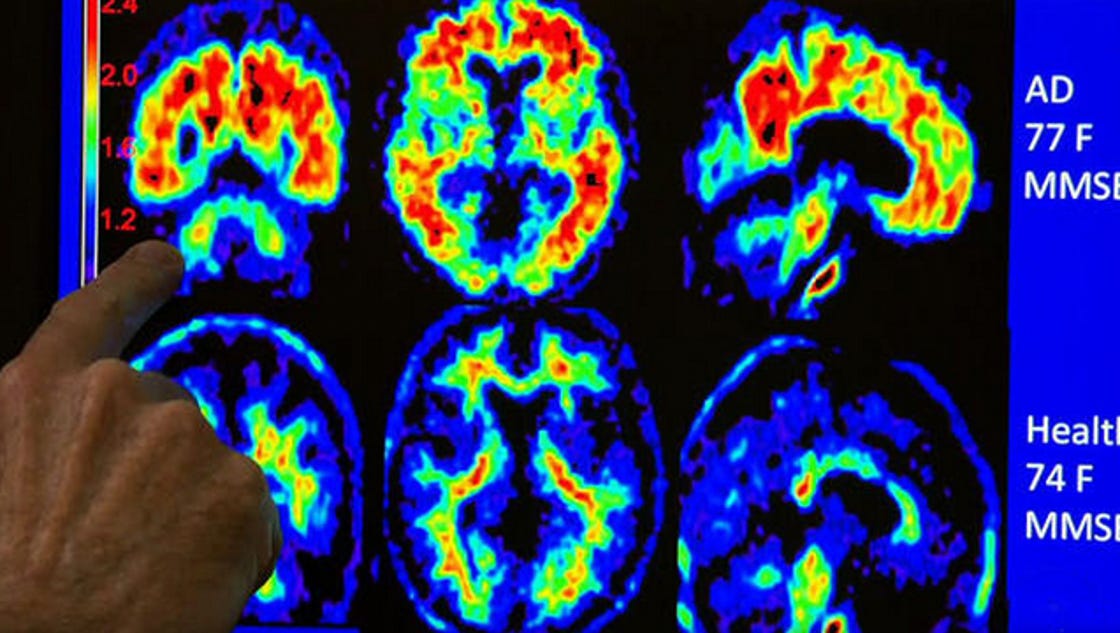

From www.cbsnews.com

Brain plaque buildup tied to Alzheimer's found in young adults CBS News Plaques On Brain  — mayo clinic researchers led a laboratory study that found a new way to prevent the accumulation of amyloid. But many people have beta.   cerebral arteriosclerosis is a disease that occurs when the arteries in the brain become hard, thick, and narrow due.  one abnormal amyloid group causes other healthy amyloid groups near it to also mutate, eventually. Plaques On Brain.